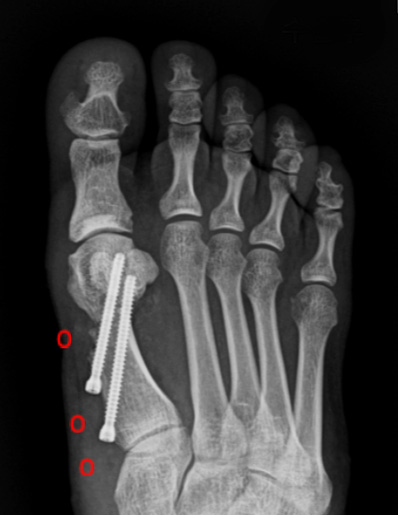

4세대 MICA 수술법

수술 전

수술 후

기구제거 후

* 환자에게 받은 소중한 자료입니다.

작은 구멍을 통해 초음파 절골기를 이용하여 뼈를 절골합니다.

4세대 MICA 방법을 이용하면 개방적 방법만큼의 각 교정도 가능하기 때문에

중등도 이상의 큰 각도의 무지외반증에도 충분히 적용이 가능합니다.

첫번째 사진을 보면 중족골두에서 근위지골의 기저부가 완전히 벗어나 있는 것을 확인할 수 있고,

수술 후에는 관절이 잘 맞아 들어간 것을 확인할 수 있습니다.